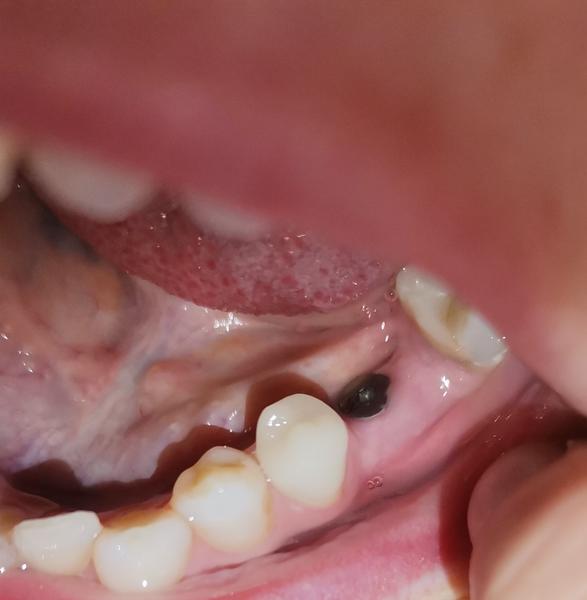

Zle zavedený zubný implantát

Ahojte. Pred rokom som si dala zaviesť zubný implantát. Zubár mi ho však zavŕtal veľmi vysoko a zasahuje až do prínosovej dutiny. Zistila som to tak, že som dostala silnejšiu nádchu a odvtedy má dutiny a pravá strana tváre stále bolí. Myslela som že mám problém so zubom tak som bola u zubárky. Tá mi urobila rentgen A hovorí mi že v implantát je zavŕtaný až do prínosovej dutiny. Chcem sa opýtať či sa s tým niekto stretol. Dá sa to odvŕtať alebo musí nanovo vybrať von ten implantát a zase nanovo navrtat? Ďakujem

@stanulienkat oki, akurát, že on mi potom aj robil RTG a tvrdí, z vidíte nieje to v dutine ešte. A sa mi aj zdalo, že je to na Tom RTG akosi vysoko. To len iná zubárka mi vraví, že veď to máte v dutine. Ja už som taká narušená na neho, lebo ani odtlačky dobre neurobil a musel to obrúsovat.